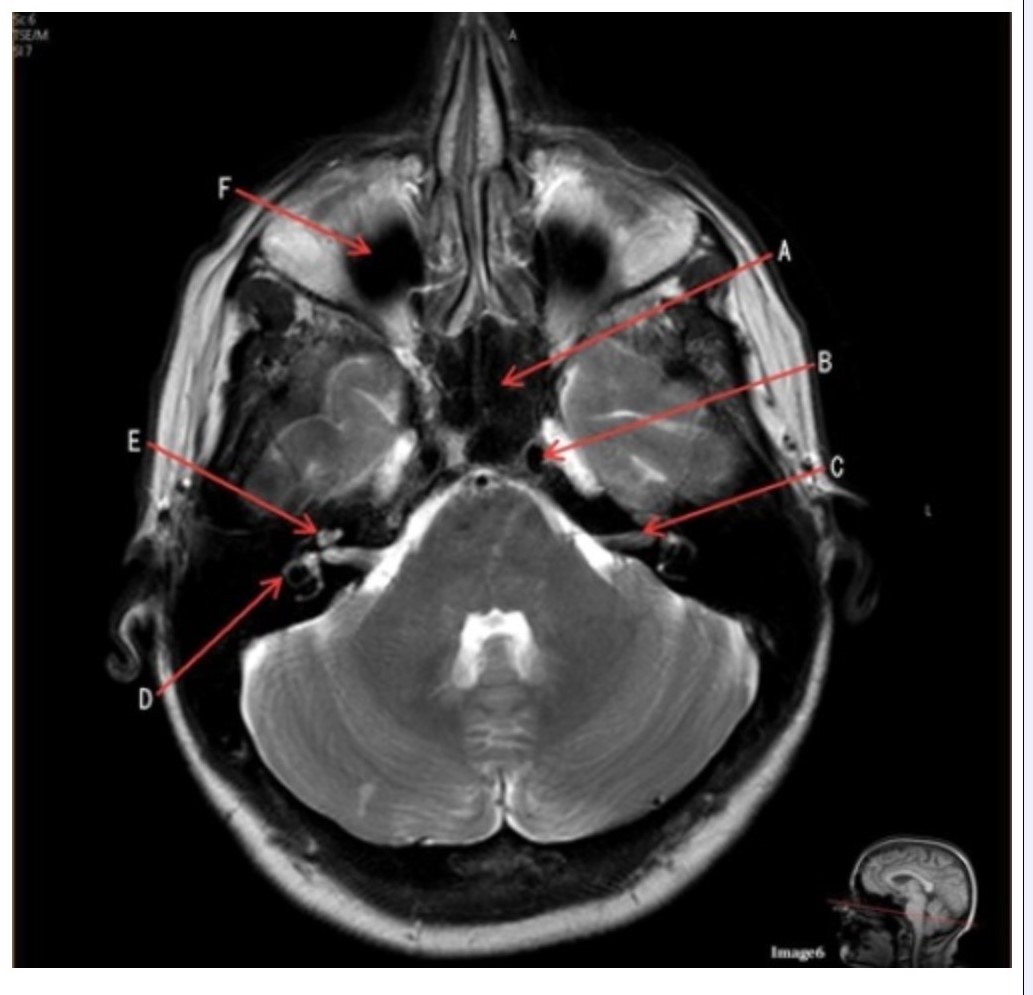

Letter A in Image 6 is pointing to:

A. Maxillary sinus

B. Sphenoid sinus

C. Frontal sinus

D. Internal carotid artery

Letter C in Image 6 is pointing to:

A. 7th cranial nerve

B. Cochlea

C. Trigeminal nerve

D. Semicircular canal

Letter B in Image 6 is pointing to:

A. Maxillary sinus

B. Sphenoid sinus

C. Vertebral artery

D. Internal carotid artery

Letter F in Image 6 is pointing to:

A. Maxillary sinus

B. Sphenoid sinus

C. Frontal sinus

D. Optic chiasm

Image 6 is an example of a _____ weighted sequence acquired in the _______ imaging plane.

A. T1; Axial

B. T1; Coronal

C. T2; Axial

D. T2; Coronal

E. STIR; Axial

Letter E in Image 6 is pointing to:

A. 7th cranial nerve

B. Cochlea

C. Trigeminal nerve

D. Semicircular canal